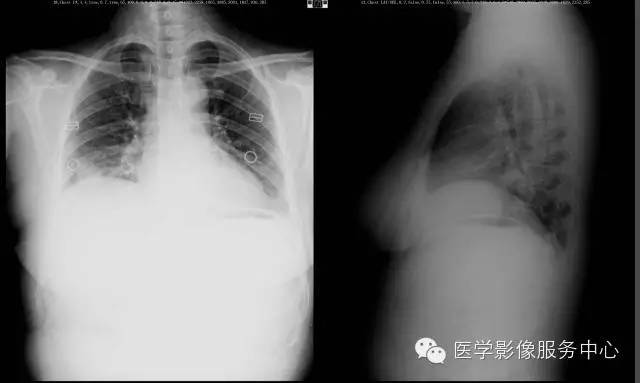

【病例】右下肺乳头状腺癌1例CT影像表现

女,49岁, 咳嗽、胸痛一周。

肺乳头状腺癌作为肺腺癌中的一个病理亚型,与肺癌的临床特征有共同之处,即发病年龄轻,病变发生部位全部位于肺的外围,以周围型为主。

病灶体积比较小,以女性居多。